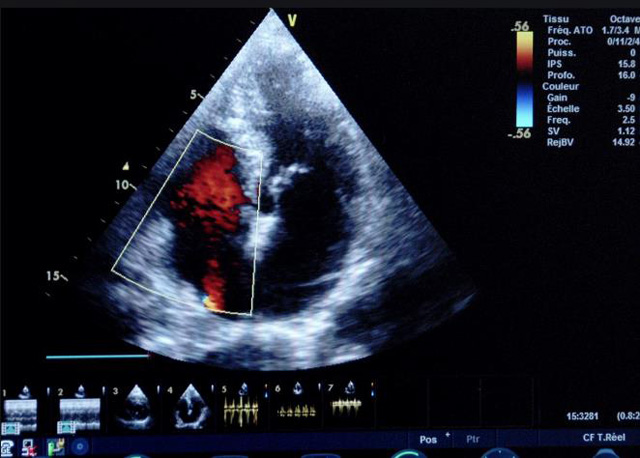

二、彩色室壁運動分析

(一)基本原理彩色室璧運動分析,從整體散射數(shù)據(jù)中識別心內(nèi)膜邊界,并與前一幀彩色不同,心臟收縮或舒張期開始到結束時心內(nèi)膜的全部過程。每一次順序顯示結束后,原來的彩色自動消失,以便進入下一個顯示過程。其結果是獲得對應于每一個心動周期的彩色顯示,描繪特定周期內(nèi)室壁運動的時間運動軌跡。

(二)操作步驟根據(jù)背向散射數(shù)據(jù)中將心內(nèi)膜運動的位移過程分類為組織或血液的原理,邊緣檢測跟蹤心內(nèi)膜和血液的界面。橙色表示收縮期的開始,收縮期不同時相逐幀顯示色彩均疊加在收縮末期最后一幀圖像中。檢查時,可按以下步驟進行:

①顯示較為理想的二維圖像,常用切面有心尖四腔心、二腔心、左心室長軸和左心室乳頭肌水平短軸切面。

②啟動AQ系統(tǒng),啟動后適當?shù)卣{(diào)節(jié)增益補償,顯示心內(nèi)膜。

③啟動CK系統(tǒng),啟動后劃定感興趣區(qū)域。同時記錄的心動圖R波頂點為舒張末期,T波終點為收縮末期,顯示RT間期的CK彩階圖,連續(xù)記錄3~ 5個心動周期。